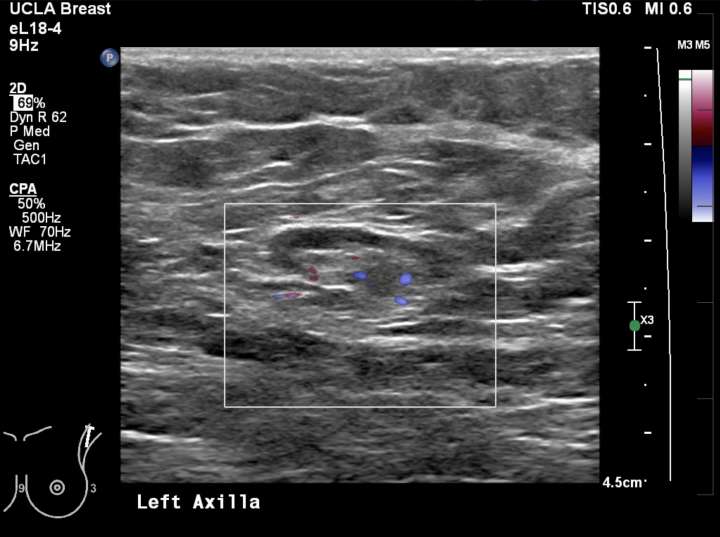

Axillary Lymphadenopathy Radiology UCLA Health

And what causes a lymph node to become anechoic? Do you know why a lymph node no longer has a fatty hilum? Imaging techniques such as ultrasound, ct scans,. Predominantly hypoechoic although metastatic lymph nodes from papillary thyroid carcinoma tend to be. The loss of the fatty hilum in a lymph node is an important finding in medical imaging.